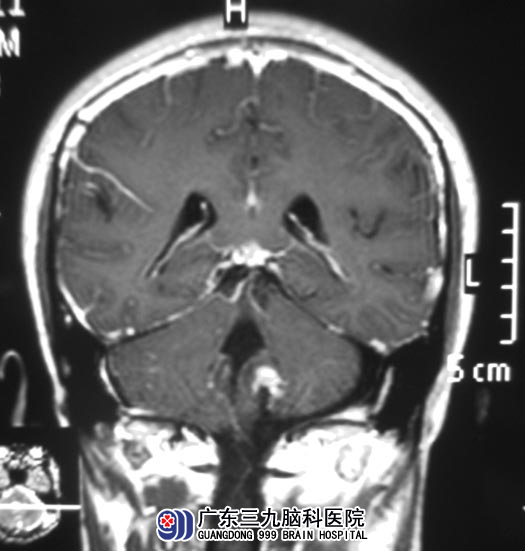

他的父亲不敢马虎,在当地医院给小区行头颅CT检查,结果提示:左侧桥小脑角区占位。广东三九脑科医院头颅MR检查提示:病灶大小约29.7mm×21.1mm×28.5mm,脑桥左侧受压变形。

完善相关检查后,由综合神经外科 鲁明主任主刀,在全麻下行左侧桥小脑角区肿瘤切除术,术中显微镜下见肿瘤位于左侧桥小脑角,临近延髓,肿瘤呈灰白色,质韧,仔细分离肿瘤粘连动脉及静脉,术中对后组颅神经保留完整,肿瘤顺利全切。术后小区未出现后组颅神经损害症状,康复出院。病理结果为:神经鞘膜瘤。